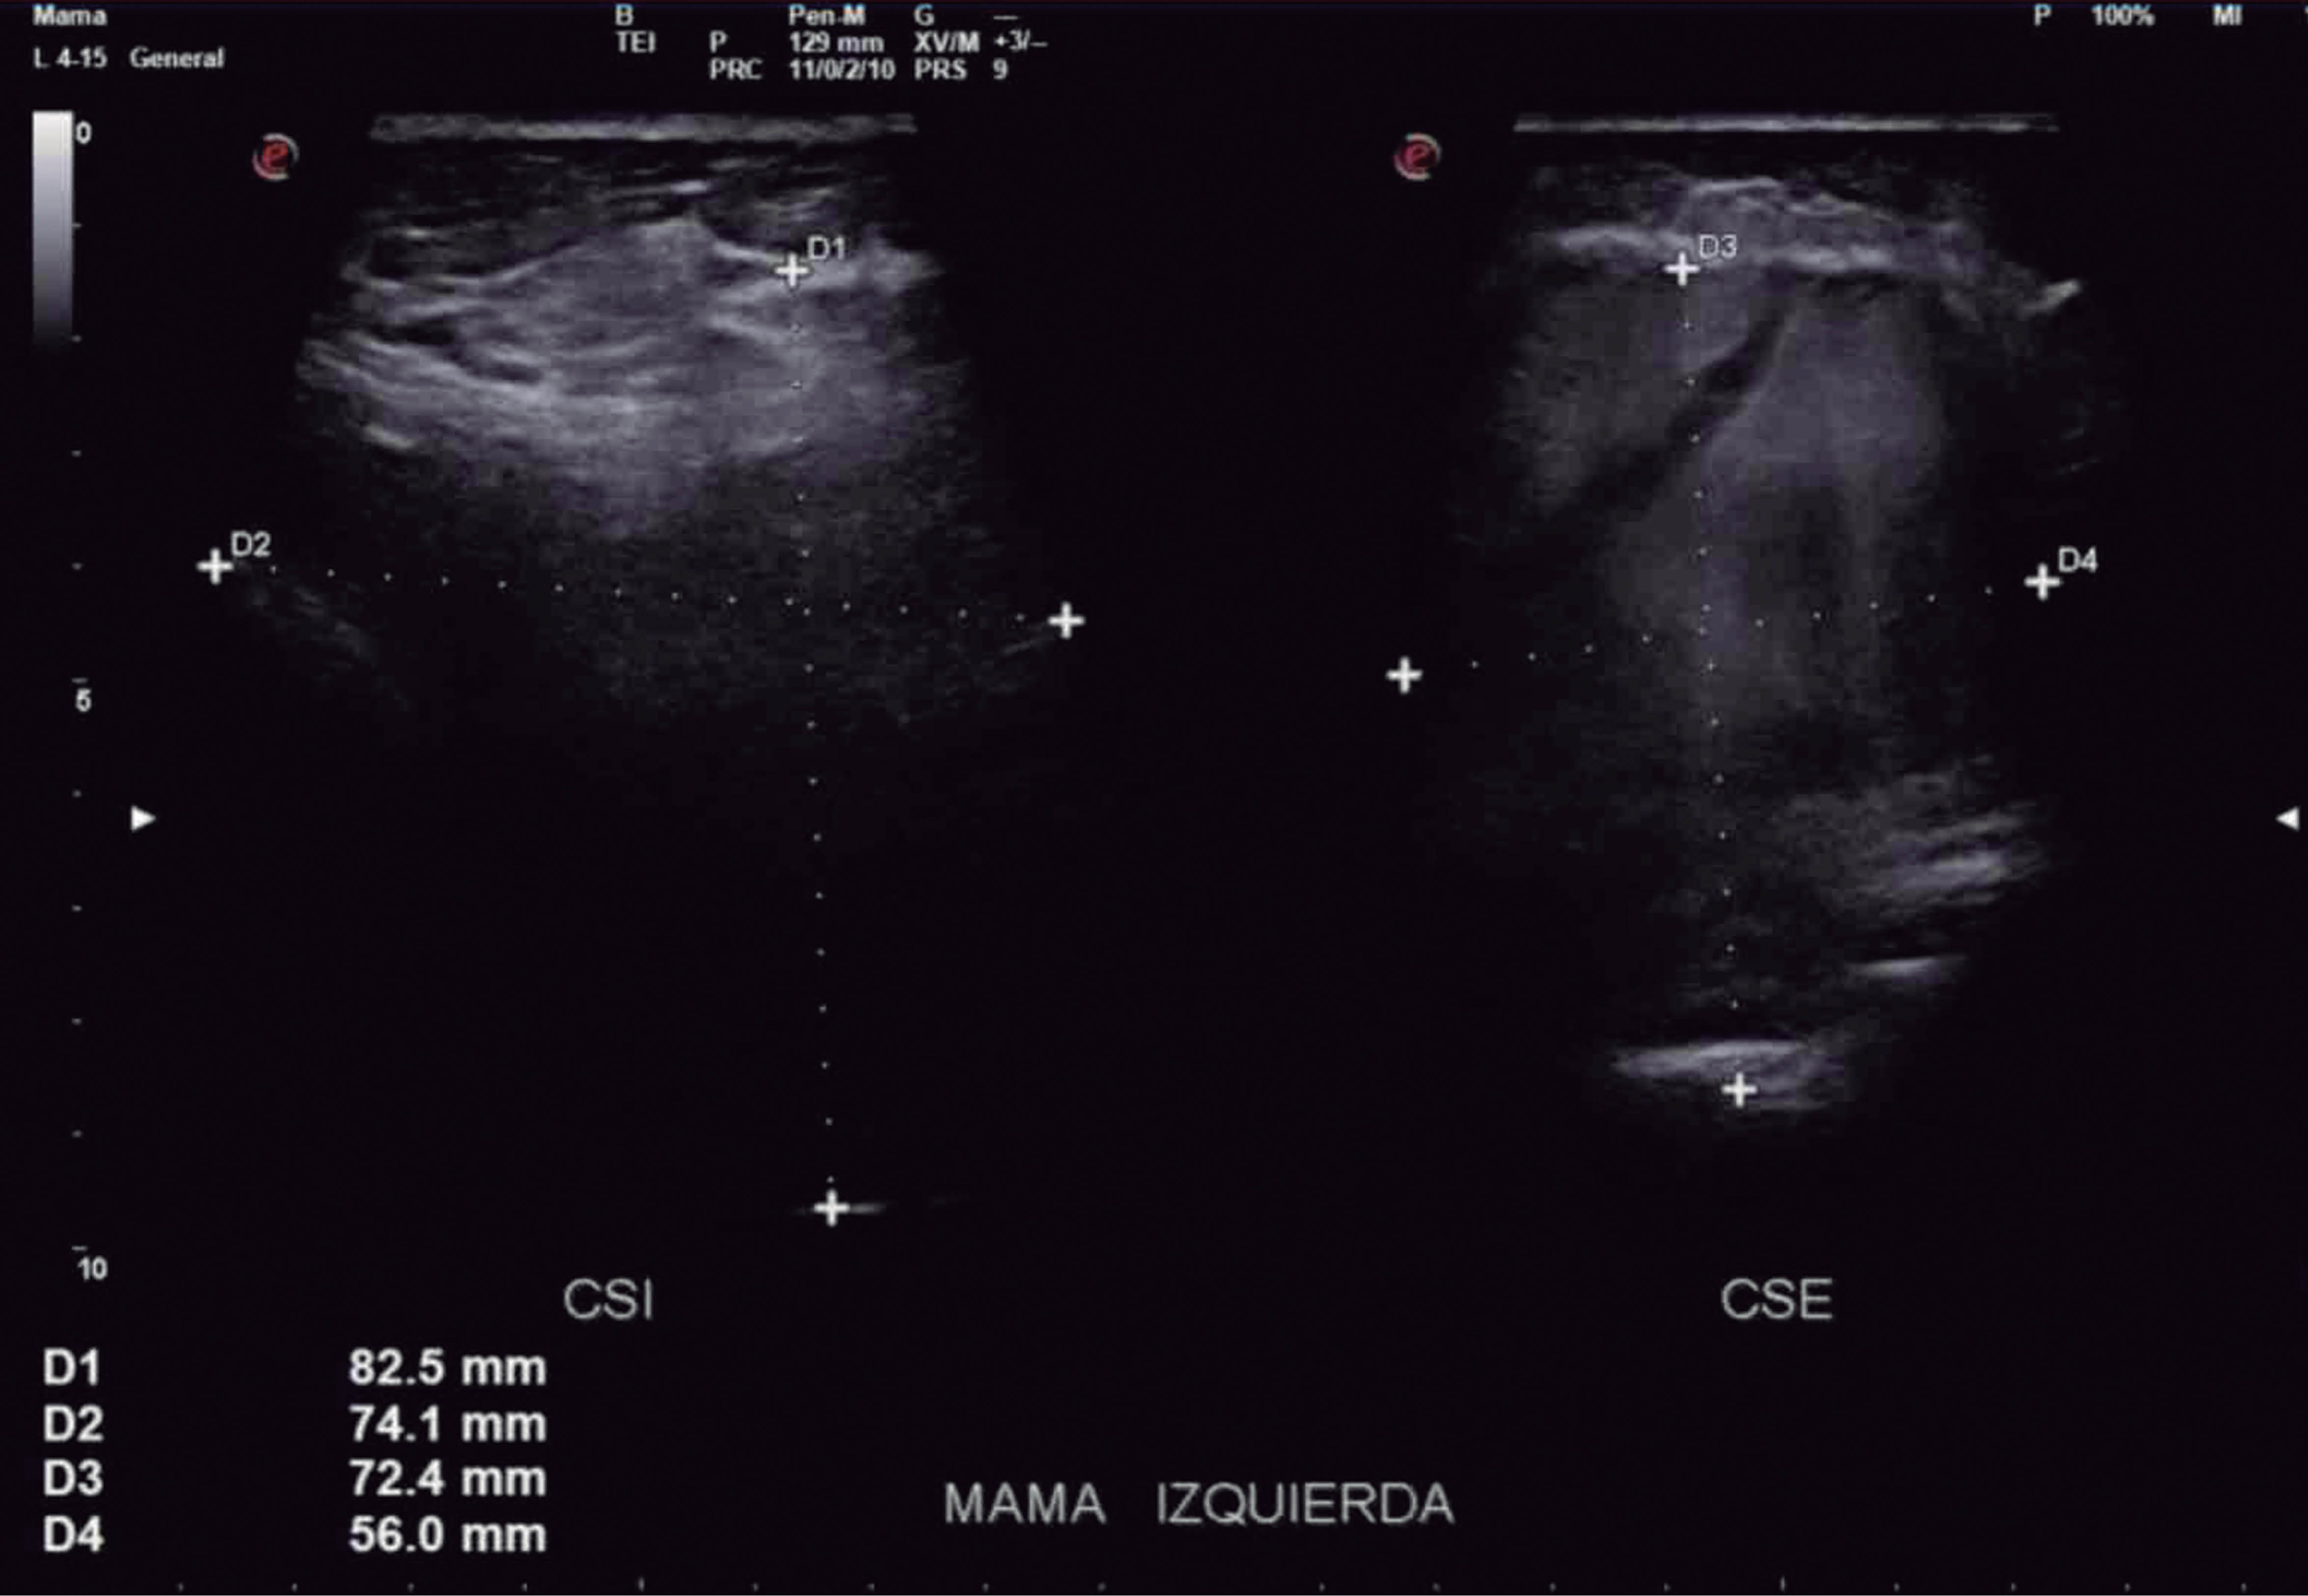

Mujer de 50 años que se había sometido previamente a un aumento de mamas en 2017 con implantes mamarios lisos de silicón de 415 mL. Dos años más tarde la paciente se presentó en el hospital refiriendo aumento progresivo de volumen y dolor de la mama izquierda. En los últimos 15 días, negó algún antecedente de trauma o uso de anticoagulantes (Figuras 1 y 2). La persona fue enviada a ultrasonido mamario (US) (Figura 3) con reporte de implante mamario izquierdo con imágenes lineales móviles y ecogénicas en el interior sugestivas de rotura intracapsular asociada con una colección subcapsular de gran volumen que cubre los cuatro cuadrantes, heterogéneo, de predominio hipoecoico, sin flujo US Doppler.

Figura 3